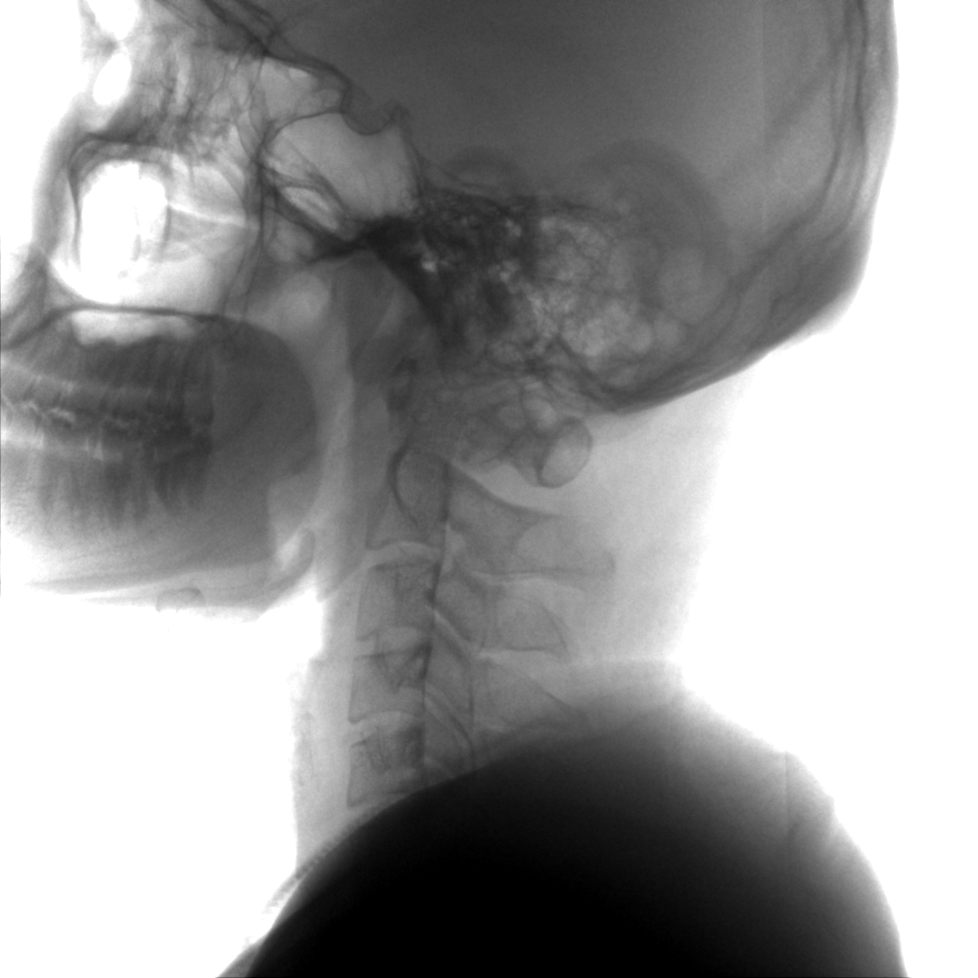

成像清晰、操作簡易、擺位便捷,主要適用于骨科、脊柱外科、矯形外科、創(chuàng)傷骨科及手術(shù)室等,能大幅度提升手術(shù)水準(zhǔn),降低手術(shù)風(fēng)險(xiǎn)和并發(fā)癥的概率。

術(shù)中三維成像和橫斷面圖像提供多角度的手術(shù)診斷信息,輔助醫(yī)生進(jìn)行術(shù)中評(píng)估判斷,諸如骨折復(fù)位情況和內(nèi)植入螺釘?shù)某叽绾臀恢茫o助手術(shù)更好地完成。

提供更大的術(shù)中三維成像視野,采集更多圖像信息,可一次拍全全段頸椎、全段腰椎、七節(jié)胸椎、雙側(cè)骶髂關(guān)節(jié)、股骨頭及單側(cè)盆骨。